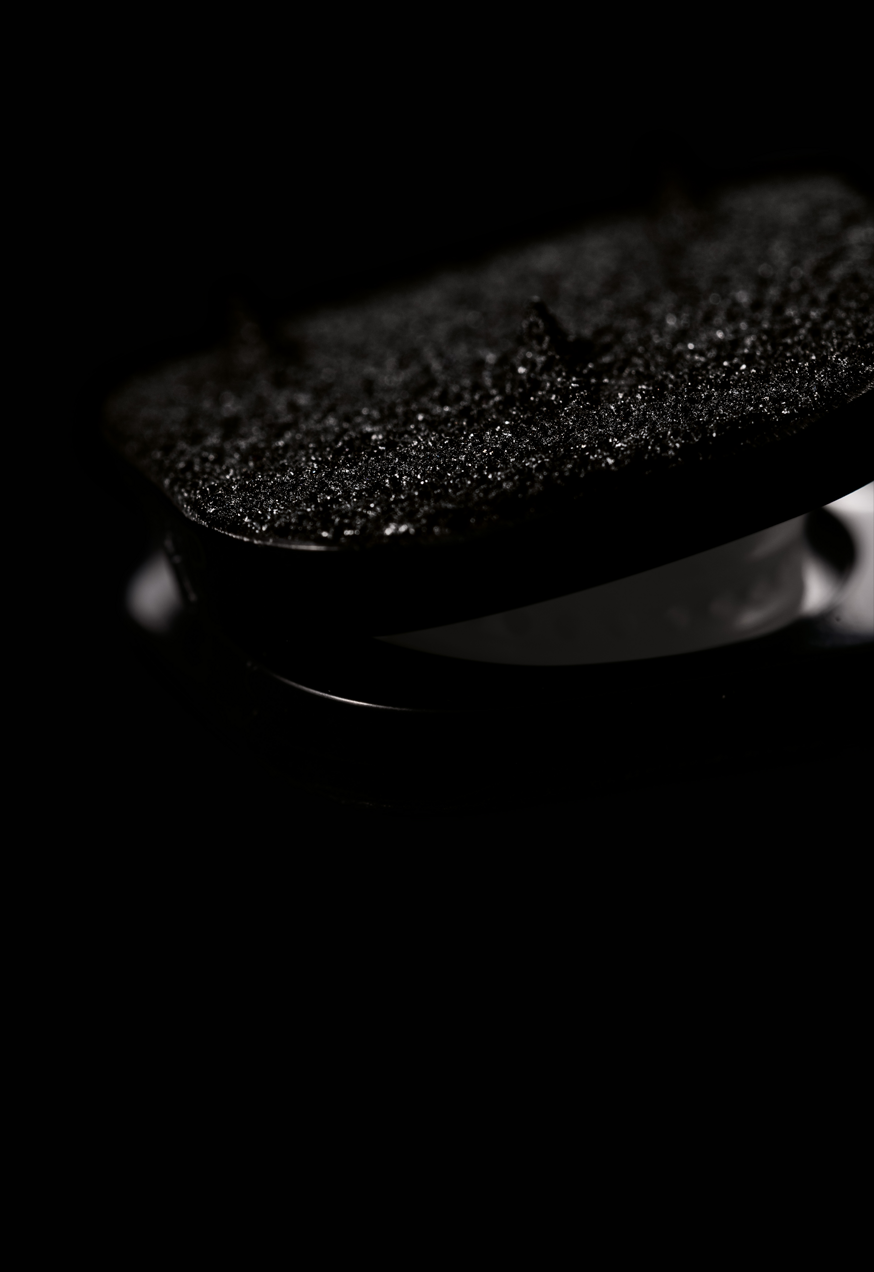

El recubrimiento de Diamolith (DLC) de las placas de titanio reduce los artefactos en la RM, lo cual permite un mejor seguimiento postoperatorio.